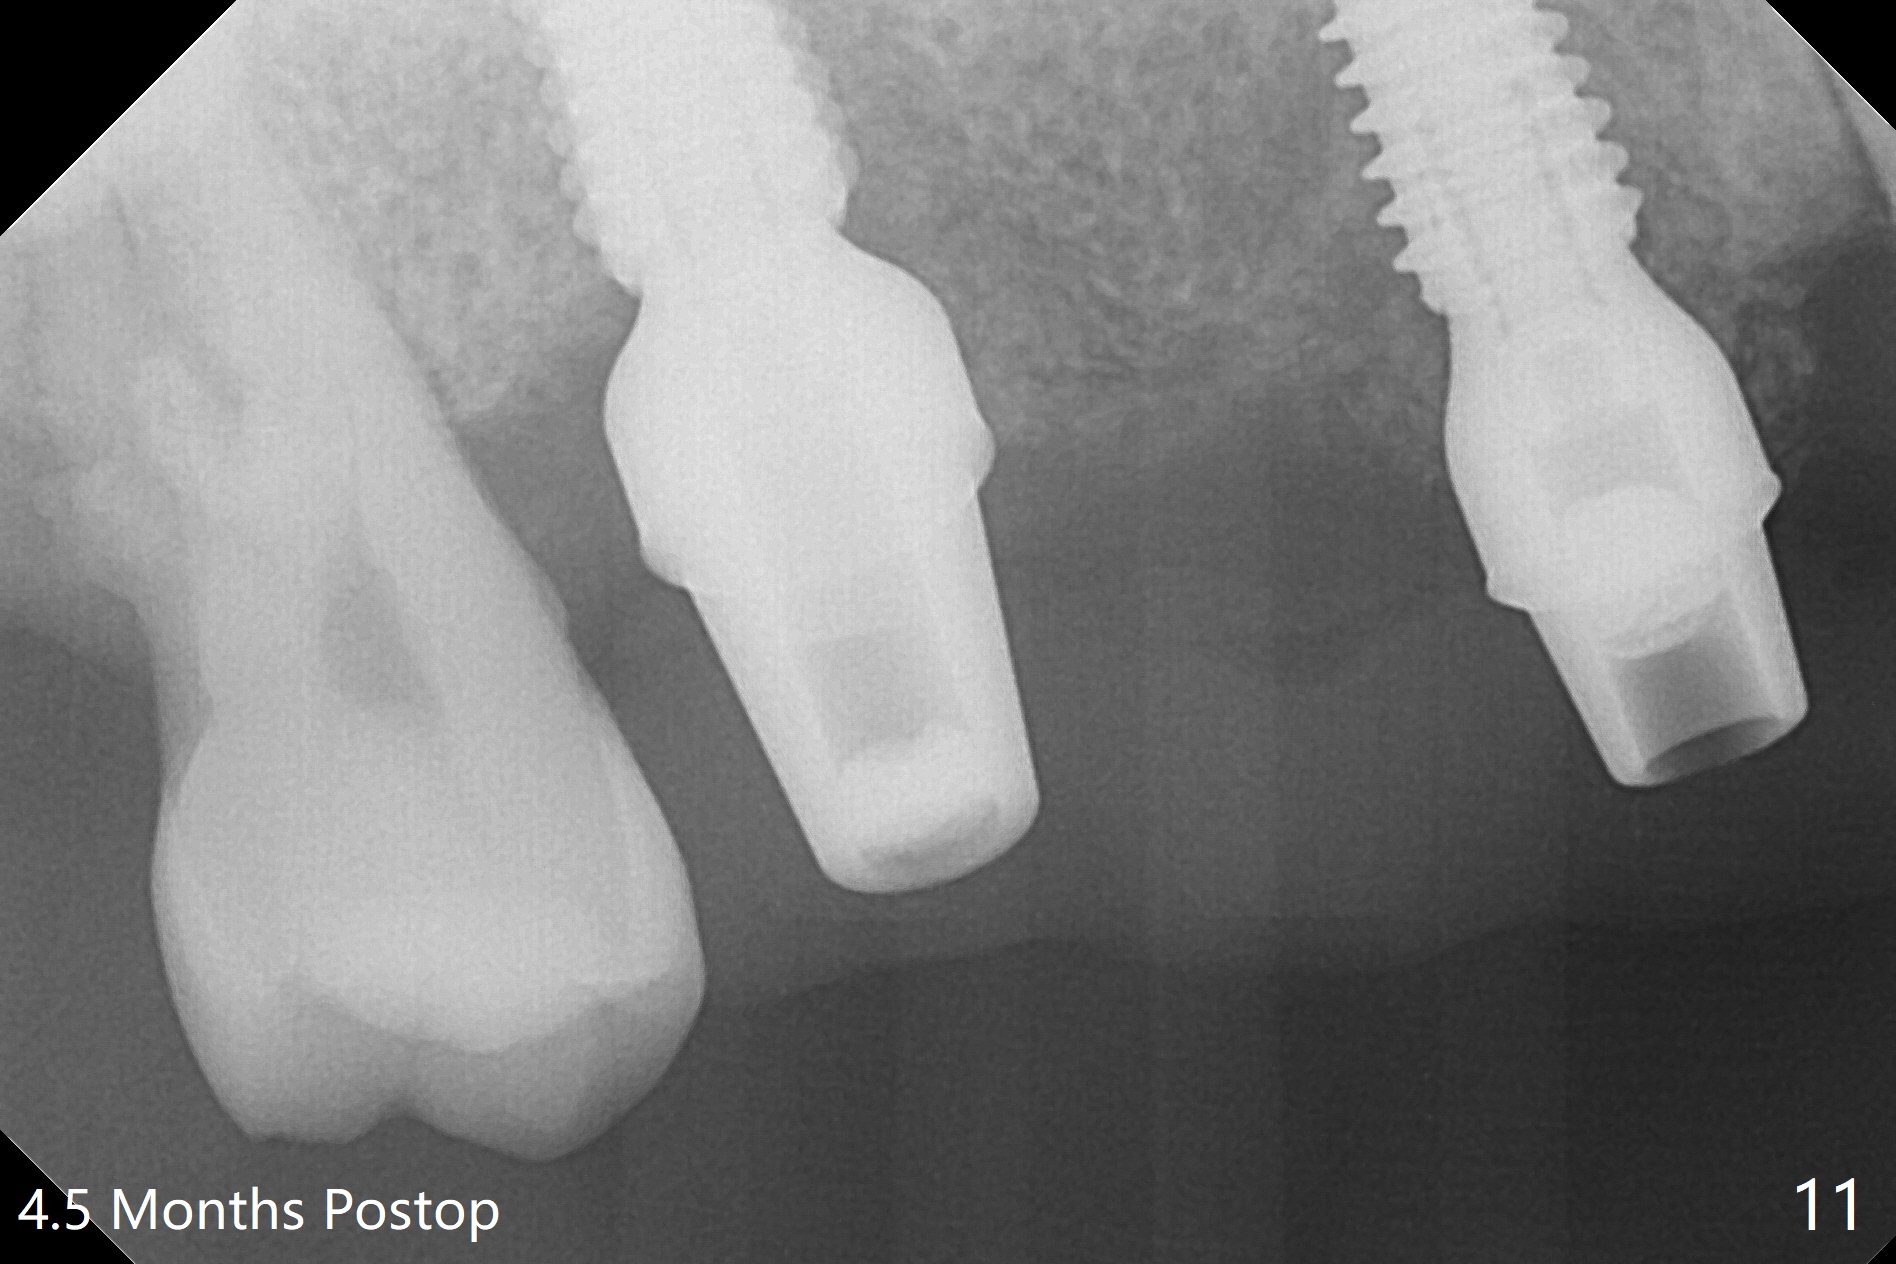

The 36-year-old man (ex-smoker, quit for 4-5 years) insists upon #3 and 5 extraction first for implants, in spite of more severe infection at #7, 14,19,30 (Fig.1-4). The gingiva around #23-26 implants is healthy 3 weeks postop (Fig.5). The initial depths at #3 and 5 are 8.5 mm (bone-level) and 18 mmm (gingiva-level (13 mm (implant length) + 5 mm cuff), respectively. When a drill penetrates the sinus floor, confirm the depth. After use of 3.8 mm drill, 4.5 mm tap drill is inserted at #3 without stability, while a 4.5x13 mm implant is placed at #5 with primary stability (Fig.6,7). Then a 5x11.5 mm is placed at #3 subcrestal proximally after sinus lift with Vanilla graft (without sinus membrane perforation; Fig.8). The implant at #5 is seated ~1 mm deeper (subcrestal mesially (^^); supracrestal distally (^)); allograft is placed around the implants prior to insertion of 6.5x7(5) and 5.5x4(5) mm abutments; last more allograft is added (Fig.9 *, 10). The implants seem to have been osteointegrated 4.5 months postop (Fig.11,12). The gingiva is healthy around the implants without bone loss 3 months post cementation (Fig.13,14).